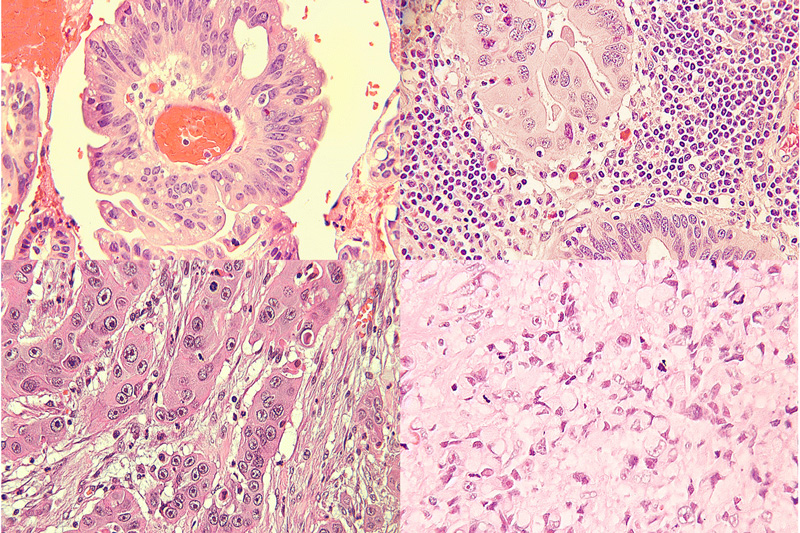

Awesome Image Awesome Image